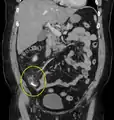

![]() حصاة برازية مشاراً إليها بالسهم والتي تسببت بالتهاب في الزائدة الدودية. حصاة برازية مشاراً إليها بالسهم والتي تسببت بالتهاب في الزائدة الدودية. | |

أشعة مقطعية تُظهر حصاة برازية.